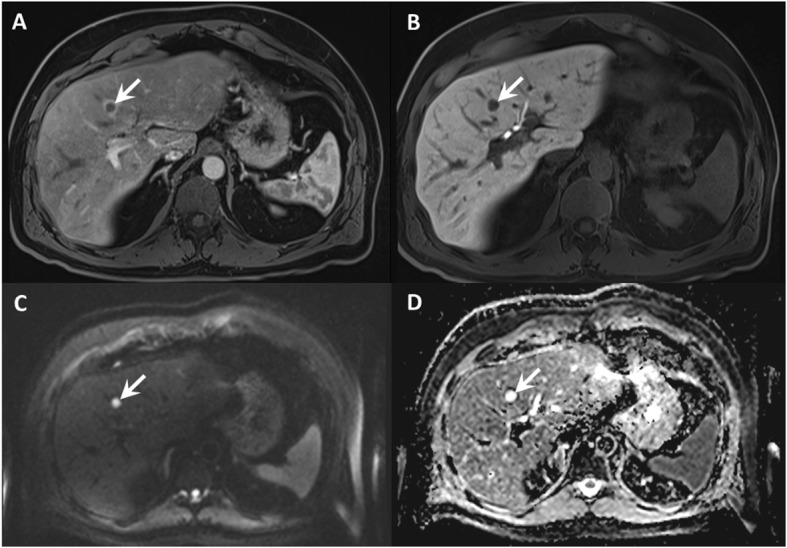

Of note, one patient in the investigated cohort did not show any metastatic lesions on 18F-DOPA-PET/CT but one metastasis (category 5 lesion) on multiparametric liver MRI. Of the 152 metastases detected on multiparametric MRI, 84 (55% of all detected metastases) demonstrated a diffusion restriction. However, a significant proportion (56/152, 37%) of the detected metastases demonstrated a brisk arterial rim enhancement and a cystic centre, resulting in T2-shine through (Fig. 7). ADC quantification was possible for 28 lesions with a diffusion restriction and clear, definable correlate on ADC maps. The median value of these lesions was 0.778 × 10− 3 mm2/s with an interquartile range of 0.723 to 0.912 × 10− 3 mm2/s. For a major proportion (56/84, 67%) of liver lesions, a clear delineation on ADC was not possible due to small lesion size and artifacts (e. g., subcapsular localisation resulting in susceptibility artifacts).

Fig. 7.

Lesion detection on contrast enhanced images compared to DWI and ADC maps. a, b T1 GRE fs with arterial and hepatobiliary phase. c, d DWI, b800 and ADC map. Contrast enhanced T1 images show a centrally hypointense lesion (arrow) with a hyperenhancing rim in the arterial phase and no contrast uptake in the hepatobiliary phase, indicating a partially cystic metastasis (a and b). Note the T2-shine through on DWI due to its cystic character (c and d)